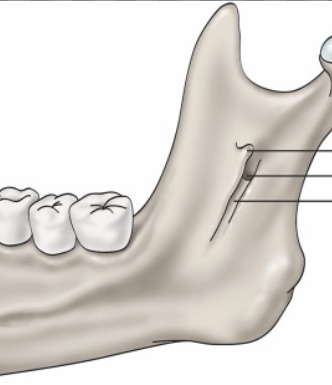

mandibular foramen

round hole on lingual aspect of ramus mandible

radiolucent, not seen intraoral

what is this, its description and its appearance on images- 1st line

lingula

small tongue shaped projection seen adjacent to mandibular foramen

radiopacity, not seen intraoral

mandibular canal

tubelike passageway thru bone that travels within body or length of mandible

radiolucent band outlined by two thin radiopaque lines representing cortical walls of cancal, may be seen on intraoral